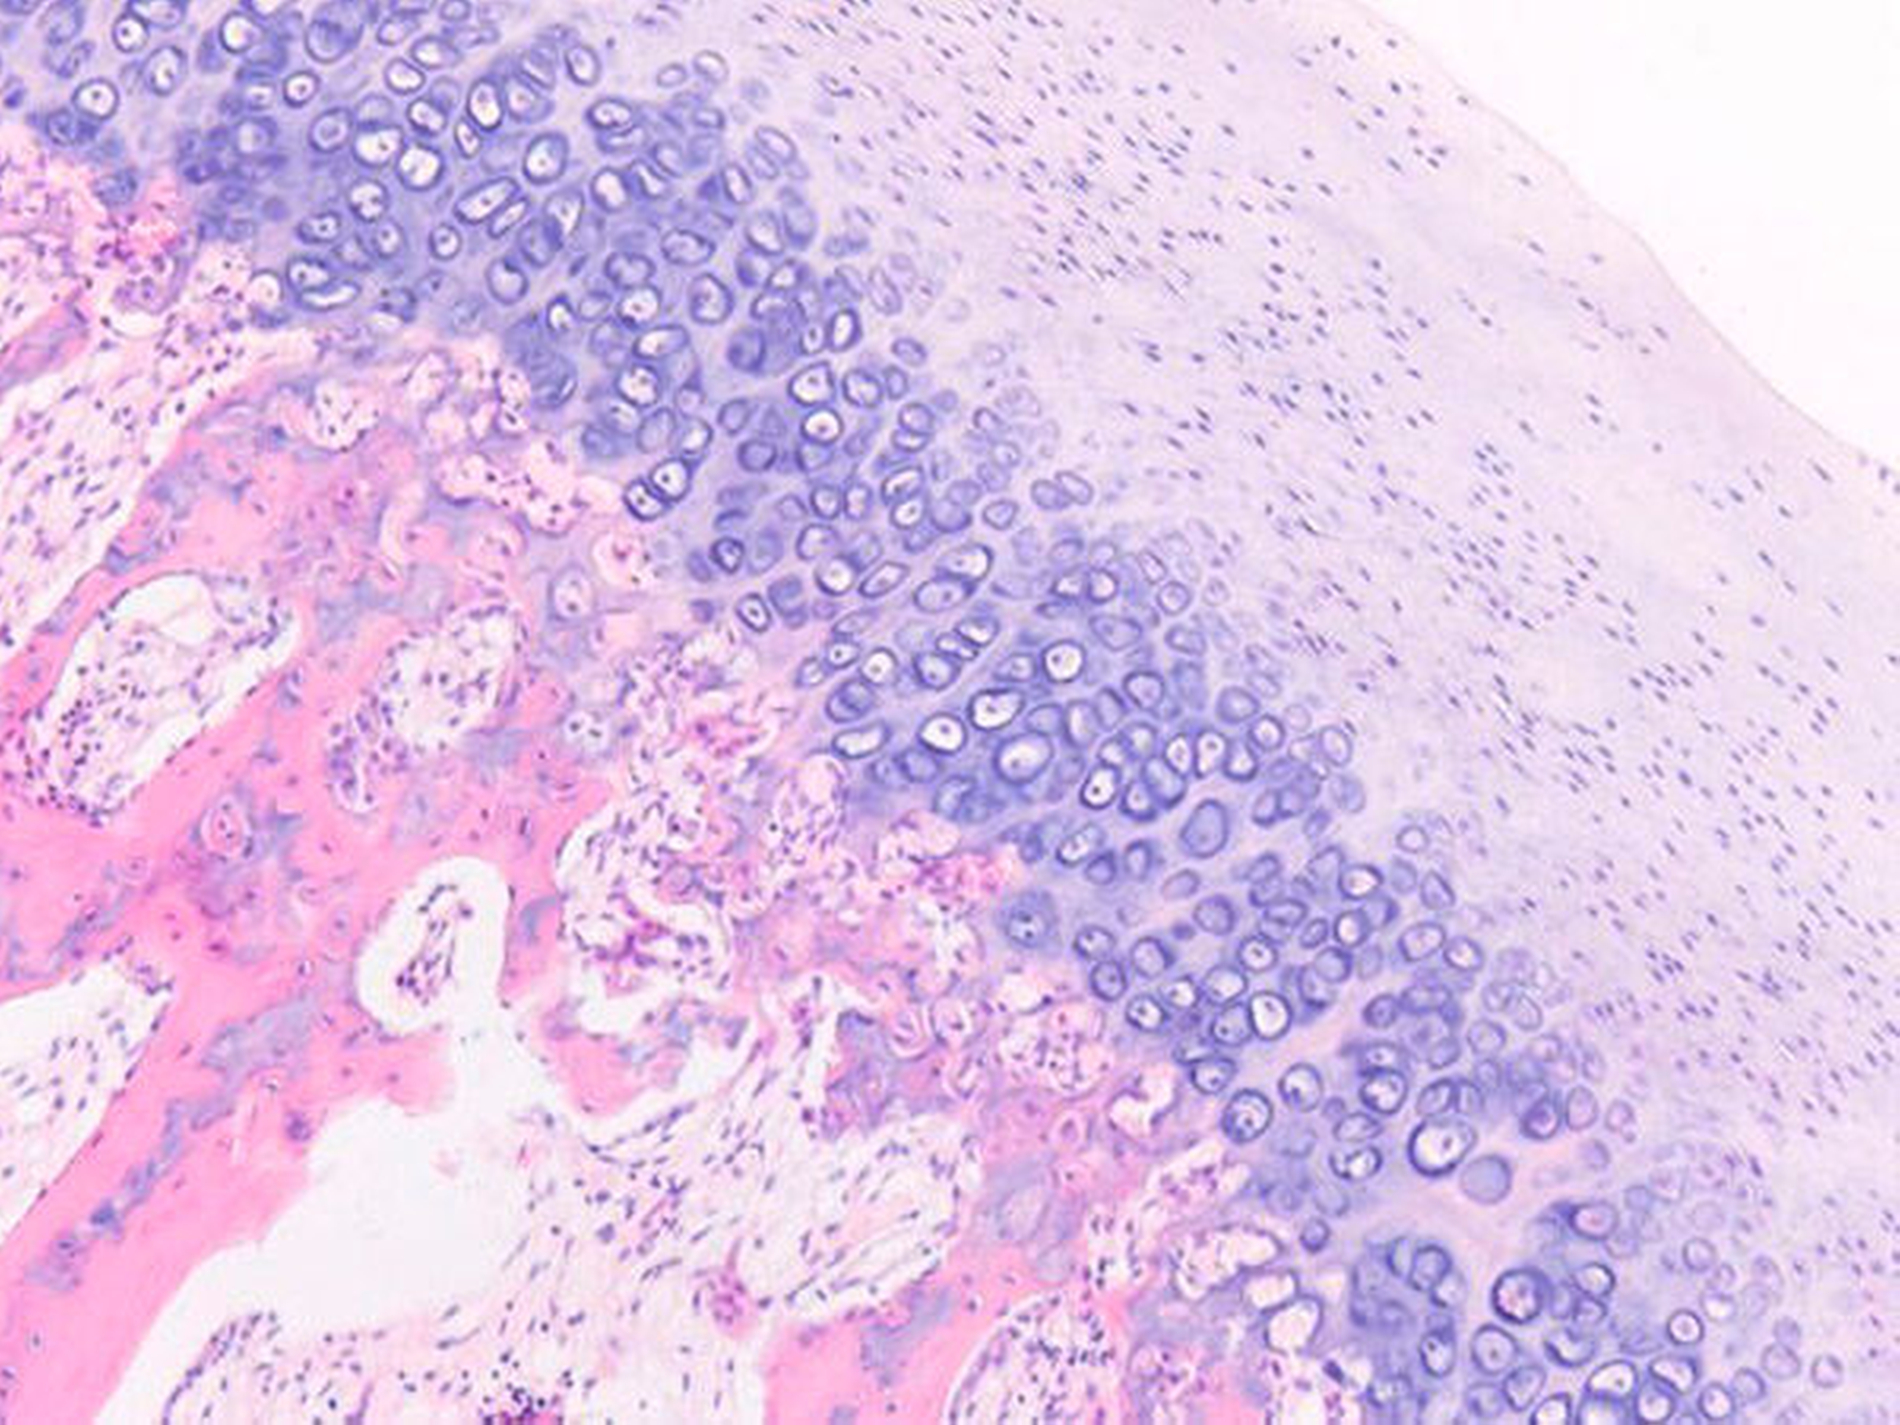

Die Patientin wurde in der Folge stationär aufgenommen und es erfolgte aufgrund der aktiven kondylären Hyperplasie eine hohe Kondylektomie rechts über einen präauriculären Zugang in Allgemeinanästhesie (Abbildung 4). Postoperative Komplikationen ergaben sich keine. Die Patientin war subjektiv beschwerdefrei, der Neurostatus unauffällig und die Nonokklusion im rechten Eck-/ Seitenzahnbereich deutlich gemindert. Eine Elongationsschutzschiene wurde in Absprache mit dem Kieferorthopäden angefertigt und eingegliedert. Im Rahmen der pathohistologischen Begutachtung des Resektats konnte der Verdacht einer kondylären Hyperplasie bestätigt werden (Abbildung 5).